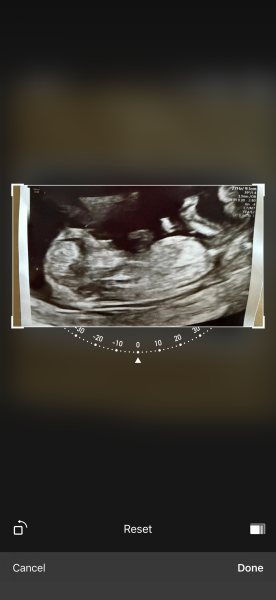

12 scan can you help me guess the gender 💙💖

Just had my 12 ultrasound found out I am 13weeks. Really eager to find out the gender. I have a scan booked but any guess would be appreciated. My last baby you could see the nub so clearly on the first scan . But I can’t make anything out on this one 🤦‍♀️